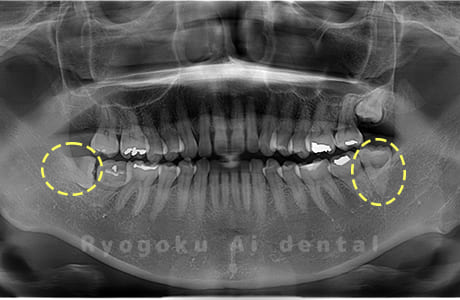

Case01

- 原因

- 水平埋伏智歯

- 治療内容

- 下顎の水平埋伏智歯を抜歯

<リスク・副作用>

手術後は痛み、腫れ、痺れなどの副作用が生じる場合があります。